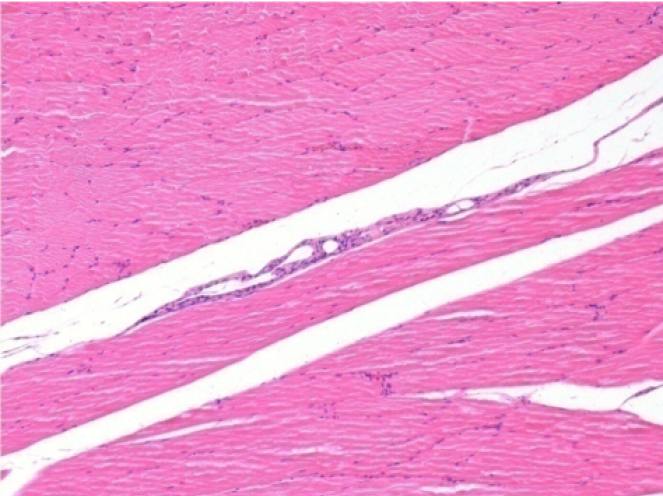

Histology

On Wistar rats

Courtesy of Lab of Pathology Department on Medicine School of Ribeirão Preto – USP

-hematoxilin-eosin

1 month after Endopeel Injection 0.1ml in the right pretibial muscle.

What is seen in black on the pictures is not a necrosis like could imagine some scientifics !

In fact, 4 conclusions have to be taken in consideration